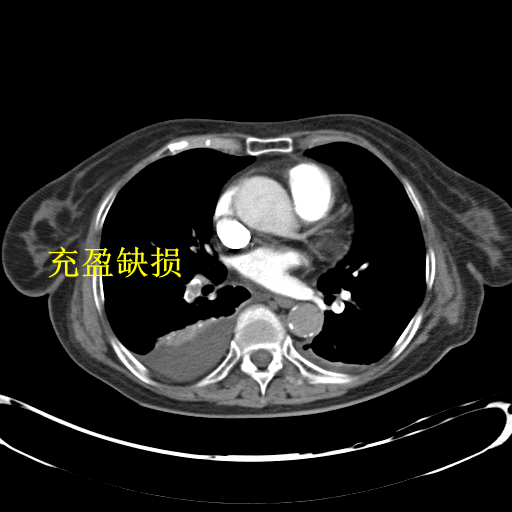

肺动脉 cta 不会看?这篇教你轻松诊断肺栓塞!